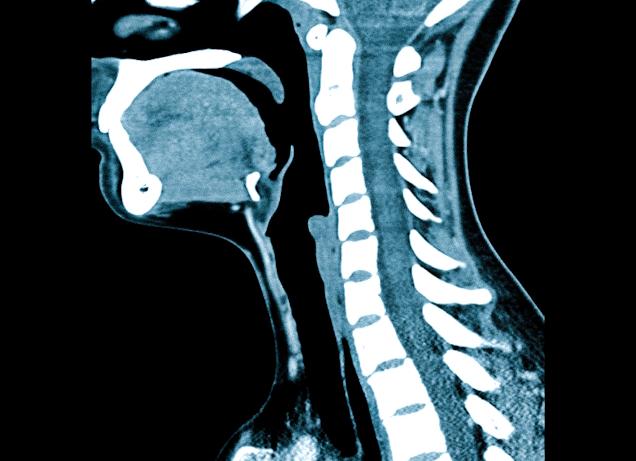

МРТ пояснично-крестцового отдела позвоночника показывает чёткое изображение соответствующей области позвоночника в мельчайших деталях. На снимке будут чётко различимы тела всех позвонков, которые попали в зону сканирования, а также межпозвонковые диски и спинной мозг, ткани, которыми они окружены. МРТ показывает такие аномалии и патологии поясничного отдела:

Преимущества такого обследования нижних отделов позвоночника заключается в получении четкого трехмерного изображения, полностью соответствующего реальной картине состояния пациента. Детально рассмотреть на снимке можно тело каждого позвонка, попавшего в область сканирования, спинномозговое вещество и межпозвоночные диски. Мягкие ткани, окружающие хребет, также станут доступны для визуализации специалисту.

МРТ поясничного отдела послойно визуализирует исследуемый участок, выполняя десятки срезов, которые компьютерная программа объединяет в одно изображение. В ходе МРТ поясничного отдела делают срезы в поперечной и саггитальной проекции толщиной 3–4 мм.

При обследовании поясничного отдела делают три проекции: две из них параллельно спинному мозгу и каждый межпозвонковый диск. Цель именно такой техники обследования – наличие изображений, несущих информацию, которые отображают поясничный отдел от правого до левого поперечного отростка. Также назначают мрт с контрастированием, что выявляет наличие посторонних образований или отклонений в пояснице и крестце.